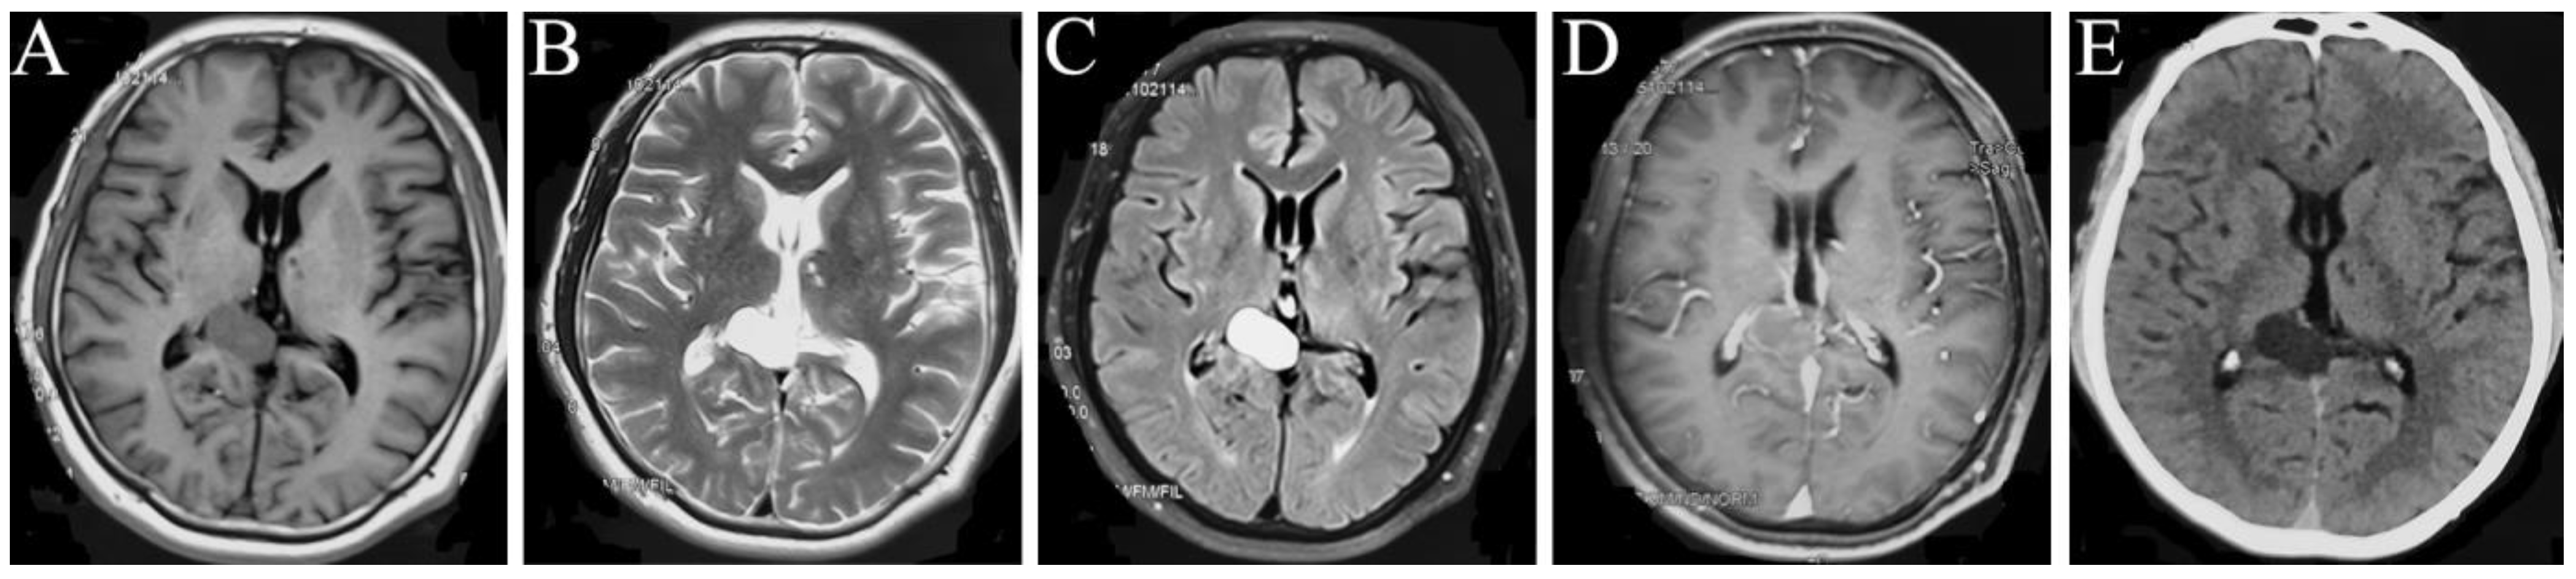

Figure 1.

MRI manifestations of the space-occupying intracranial fungal lesion on 21 October 2015. T1WI (A), T2WI (B), T2 Flair (C), Contrast-enhanced T1 (D), and CT (E) show a right occipital lobe occupation, with regular shape and clear boundary, with equally high signals on T1WI (A), predominantly high signals on T2WI (B) and T2 Flair (C), equally enhanced signal on contrast-enhanced T1 (D), and low density on CT image (E).

Imaging examination: the intracranial MRI revealed a space-occupying lesion with a regular shape and clear boundary in the right occipital lobe. Further, the corpus callosum and posterior horn of the right lateral ventricle were compressed. The occupation was 2.8 × 1.7 and 4.0 × 2.6 cm2 in size at the maximum imaging level on 21 October 2015 (Figure 1A–E) and 9 July 2020 (Figure 2A–E), respectively, with annular low signal shadow in the edge and small edema signal in the surrounding area, showing a high signal in the T2-weighted and T2 flair image and an equally high signal in the contrast-enhanced T1 image (Figure 1A–D and Figure 2A–D). The T1-weighted image of this occupation first revealed an equally low signal, and after the occupation became larger, it demonstrated a high signal (Figure 1A and Figure 2A). Moreover, the susceptibility-weighted imaging (SWI) examination found no vascular diseases (Figure 2E), and the CT revealed a low density of this occupation (Figure 1E).